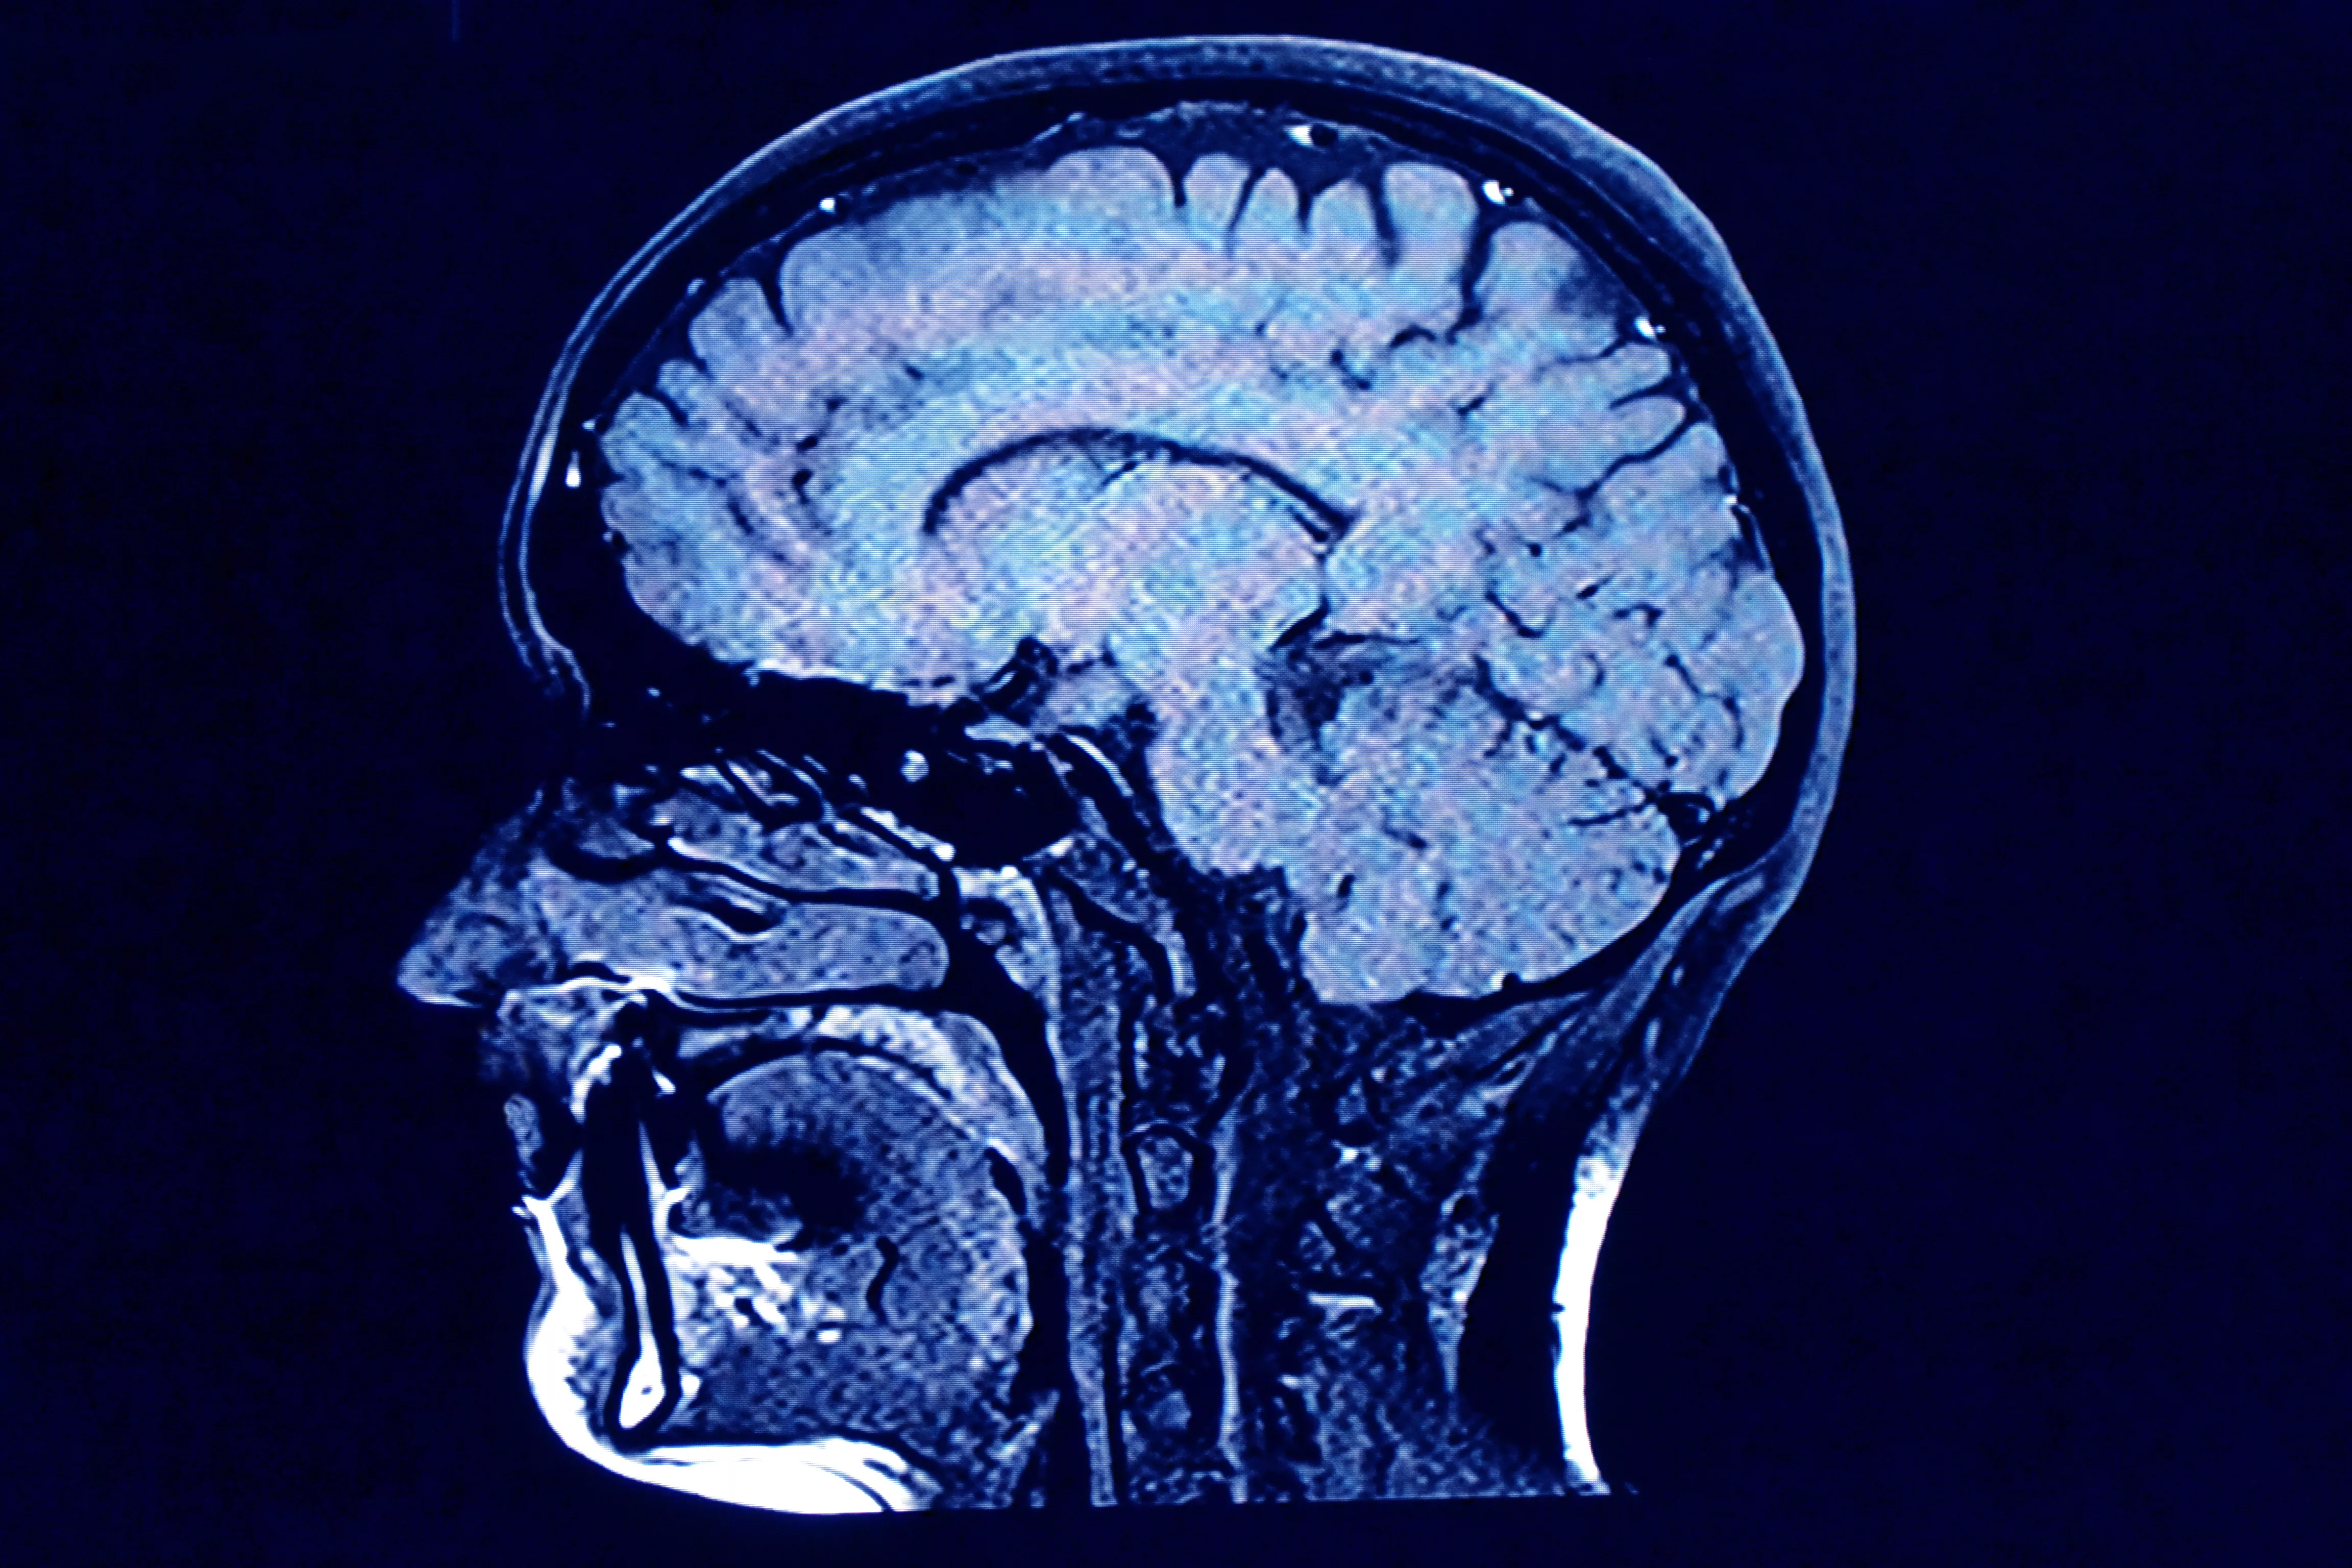

The family was shocked when they were presented with the MRI of her brain. Amanda said:

There was atrophy of the brain - it was basically wasting away. She was like an old dementia patient with lots of blank spaces in her brain.